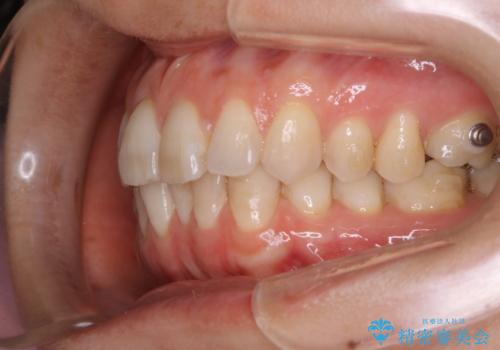

- 下の前歯のがたつきが気になるとの事でご相談にいらした患者様です。

元々はリンガルブラケットをご希望されていましたが、モニター制度を利用してインビザラインによる治療を行いました。

インビザラインFULLで奥歯の噛み合わせから改善させることで、上下の真ん中位置をしっかり合わせることが出来ました。

横顔のシルエットも改善させることができ、大変喜んでいただけました。